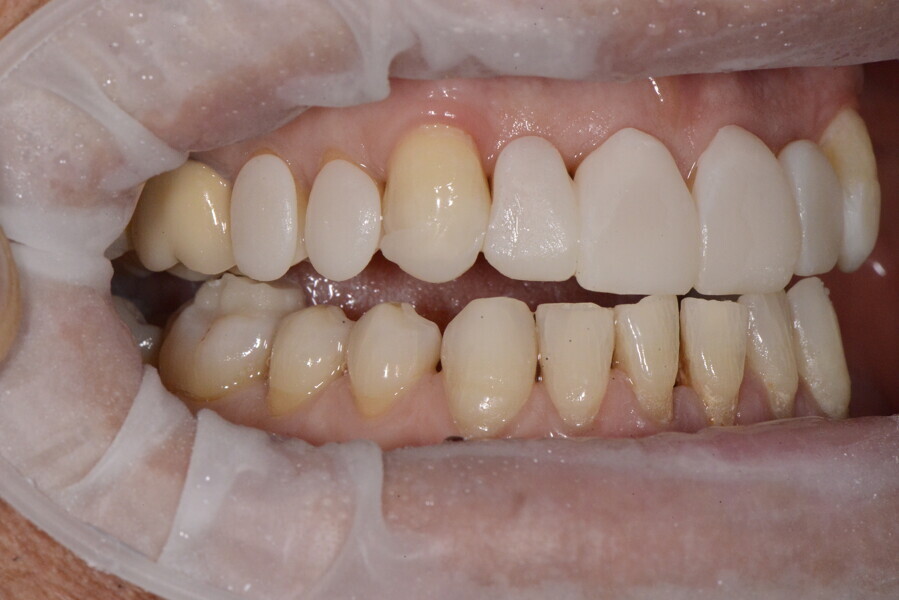

The 58-year-old patient wished to improve his oral aesthetics and function, complaining of mobility of the posterior teeth and wear of the anterior teeth. After data collection, a very complex situation was identified (Figs. 11–13):

1. severe periodontitis with poor prognosis of some teeth;

2. anterior crossbite;

3. severe wear mainly of the anterior teeth and compensatory eruption;38

4. atypical swallowing and lower posture of the tongue at rest;

5. masticatory dysfunction during the mastication test; and

6. no significant signs of temporomandibular disorder.